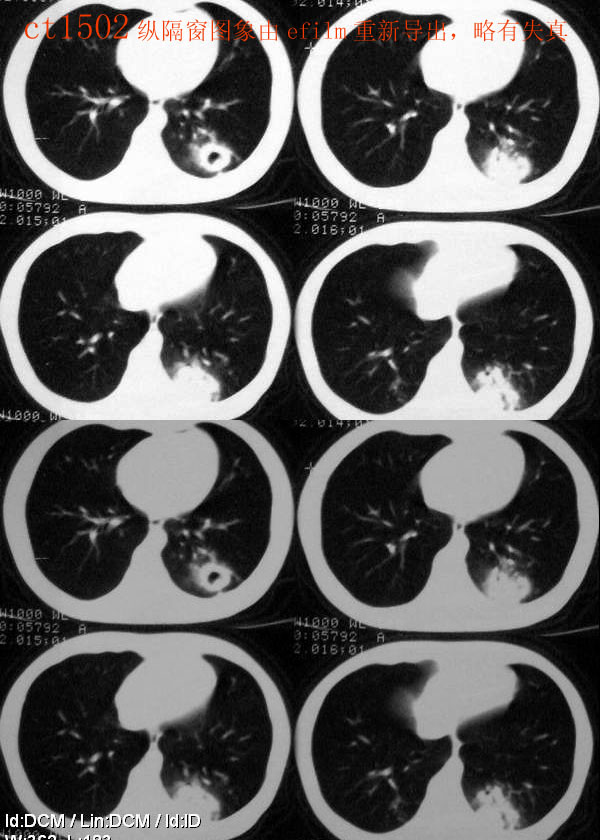

ct2533:张巍 提供 患男,24岁,胸痛数月.

穿刺活检为干酪坏死物.胸壁结核瘤!

ct1240:song7715

病人24岁,身体偏瘦,半月前曾有高烧,现无阳性体征,血项不高。透视时无意发现。

右肺结节病理结果:结核球http://www.radida.com/radinet/read.php?tid=3611

ct1585:liuwensi 提供

m,64y,体检发现右肺上叶后段孤立性结节,纵隔内未见肿大淋巴结影右肺病理是结核球